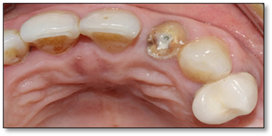

After the 3-month period required for osseointegration of the implant, the patient was seen for a digital impression for the definitive prosthesis and the fabrication of a Ti-base zirconia abutment (Figure 9), noting that the patient was under monthly clinical and radiological control. The crown was sealed, and the patient is satisfied with her crown both aesthetically and functionally (Figure 10).

Figure 9: Occlusal view of Ti-base zirconia abutment.